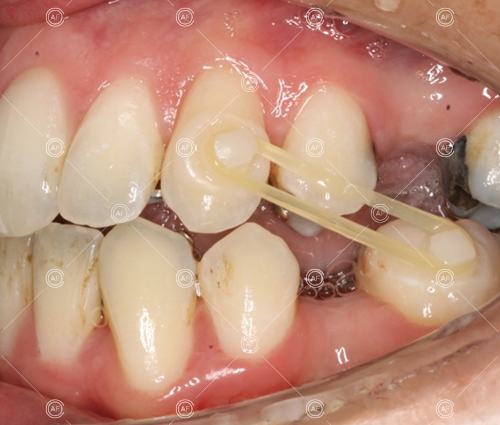

This patient (MH) began her active orthodontic treatment in October 2019 at almost 13 years old. She was unhappy with the appearance of her upper and lower teeth, and especially concerned about the unsightly nature of the high and buccally positioned upper left canine.

Buccal segments were essentially class 1 on the right hand side and a full unit class 2 on the left. This is due to buccal exclusion of the upper left 3 and mesial drift of the upper buccal segment.